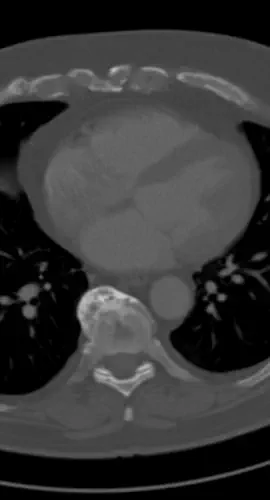

CT vom 24.07.2025

Sternum Loch